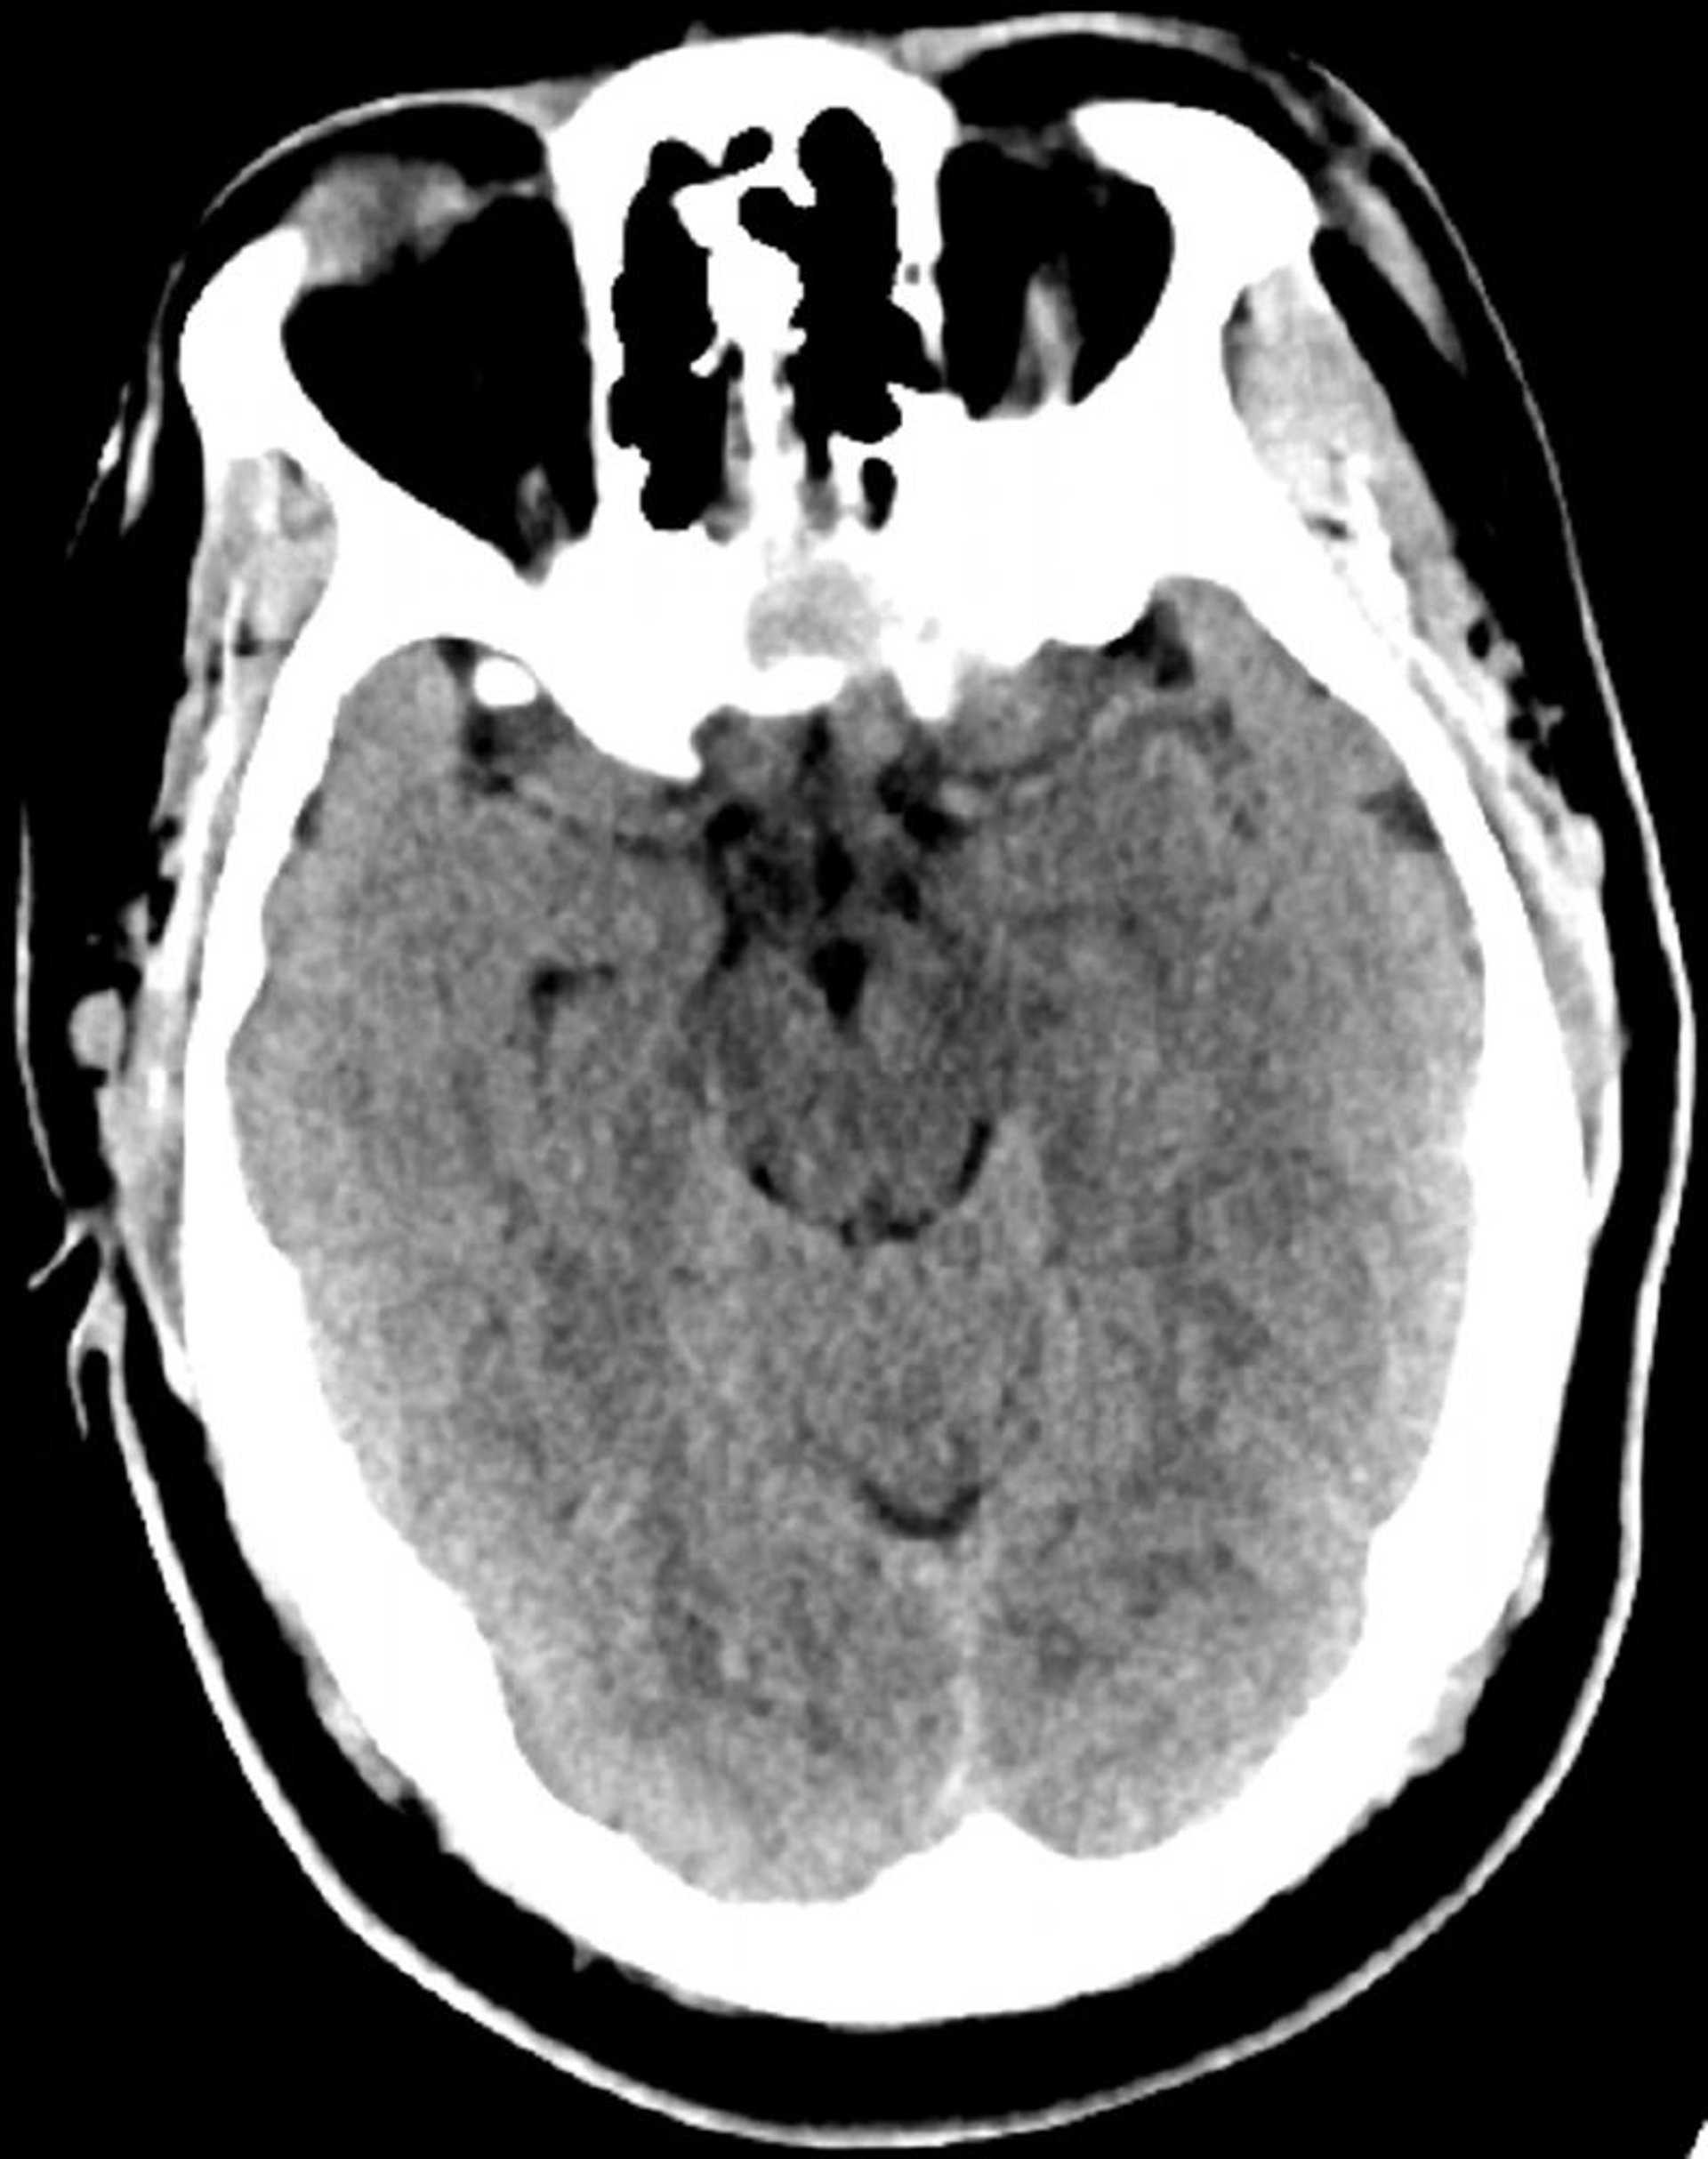

正常な頭部CT(成人,30歳)―スライド6

これは30歳の若年成人の正常な頭部CT画像である。脳実質の内外に髄液や出血はみられない。白質と灰白質の区別は維持されている。脳室の大きさと脳溝のパターンは正常である。